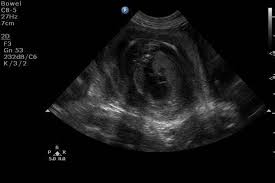

Pendant cette 3ème semaine de grossesse, l'embryon double de volume chaque jour. Elle est réalisée entre 11 semaines et 2 jours et 13 semaines et 6 jours d'aménorrhée afin de déterminer : Lors de la septième semaine de grossesse, on devrait déjà voir l'embryon à l'intérieur du sac gestationnel et, en outre, il est très probable que l'on entende le battement cardiaque de l'embryon.

1 mois de grossesse symptomes echographie precautions a prendre. La première échographie, dite de datation doit avoir lieu entre la 9ème et 11 semaine de grossesse. Echographie 4d (video) à 11 semaines de grossesse.

Coucou les filles, il y a 3 semaines j'ai été chez le gygy pour faire ma première échographie à 6sa. La troisième semaine de grossesse correspond à la 5ème semaine d'aménorrhée (5sa). Durant cette toute 1ère semaine de grossesse, rien ne laisse présager que vous attendez un heureux évènement.